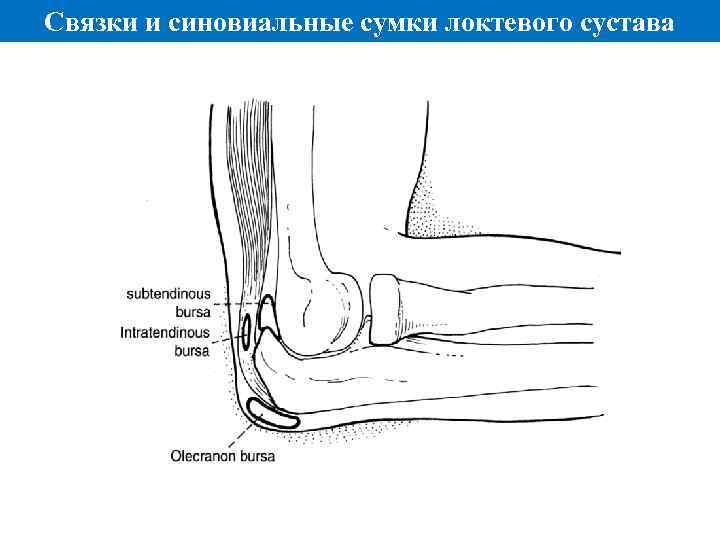

Связки и синовиальные сумки локтевого сустава

Связки и синовиальные сумки локтевого сустава